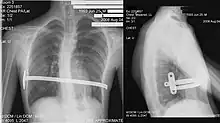

The Ravitch technique is an invasive surgery that was introduced in 1949[51] and developed in the 1950s. It involves creating an incision along the chest through which the cartilage is removed and the sternum detached. A small bar is inserted underneath the sternum to hold it up in the desired position. The bar is left implanted until the cartilage grows back, typically about six months. The bar is subsequently removed in a simple outpatient procedure; this technique is thus a two-stage procedure.

The Ravitch technique is not widely practiced because it is so invasive. It is more often used in older individuals, where the sternum has calcified when the deformity is asymmetrical, or when the less invasive Nuss procedure has proven unsuccessful.[52]

His two-stage procedure, widely known as the Nuss procedure, involves slipping in one or more concave steel bars into the chest, underneath the sternum.[56]

The bar is flipped to a convex position so as to push outward on the sternum, correcting the deformity. The bar usually stays in the body for about two years, although many surgeons are currently moving toward leaving them in for up to five years. When the bones have solidified into place, the bar is removed through outpatient surgery.